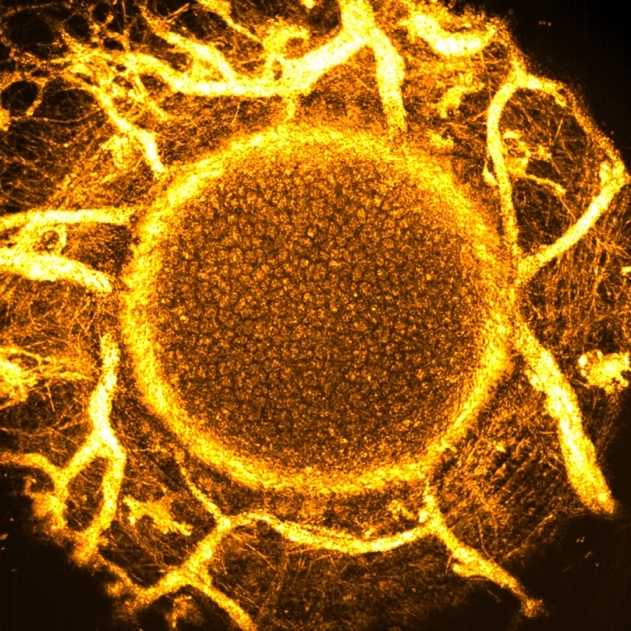

1ST

PRIZE – Prof.

Peng XIAO

(China) |

Image

title: “The

Wind

Fire

Wheel:

Non-invasive

Cellular

Imaging

of

Developing

Mouse

Lens via

Full-field

OCT” |

The crystalline

lens, critical

for ocular

optics,

maintains

transparency via

organized

architecture,

with lens

epithelial cells

(LECs) at the

anterior surface

regulating

lifelong

homeostasis.

However, dynamic

changes in lens

structures

during

development/aging

remain poorly

understood due

to inadequate

imaging tools

for deep-tissue

resolution.

Leveraging

customized

optical

coherence

tomography

(FFOCT), we

achieve

micrometer-scale

3D resolution,

enabling

high-resolution

in vivo imaging

of the intact

crystalline

lens. Here we

present the

first FFOCT

image of a

newborn mouse

lens, clearly

resolving key

structures:

LECs, anterior

lens capsule,

and the

undeveloped

tunica vasculosa

lentis. This

technology

promises

unprecedented

insights into

lens

developmental

dynamics and

early structural

abnormalities in

age-related

cataracts. |